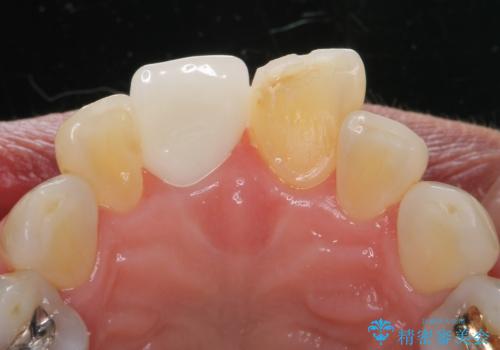

- 右上1/部分矯正:110,000円 根管治療:保険 仮歯:11,000円 ジルコニアクラウン(スペシャル):143,000円費用は治療当時の料金となります

ぶつけて埋まってしまった歯は、場合によって矯正治療で引っ張り出すことで保存することができます。

今回は歯の神経が死んでしまっていたため、根管治療後に被せ物を装着して見た目の綺麗さを回復しました。